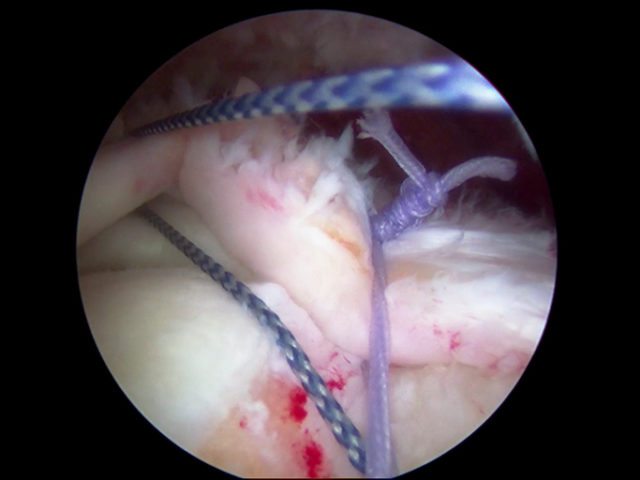

Do You Need Rotator Cuff Repair?

The shoulder is an extremely complex yet elegant piece of machinery. It happens to have the greatest range of motion of any joint in the body. However, this large range of motion can cause the shoulder to become unstable, leading to joint problems and the site of multiple injuries. Your shoulder joint is composed of…